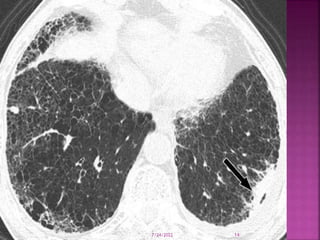

 Chest x-ray findings include small irregular

opacities, interstitial densities, ground glass

appearance, and honeycombing.